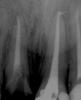

Ico Опубликовано 22 декабря, 2010 Поделиться Опубликовано 22 декабря, 2010 Для обработки каналов пользуюсь протейперами,для обтурации дают только стандартную и конусную гутту(04 и 06) и АН+.Плотно по объёму обтурировать иногда не получается-боюсь продавить силер,т.к. за пафы "ругают".Апексы стараюсь не ломать,силером только стенки обмазываю.Хочется ещё и дельту максимально закрыть.Знаю,что необходимо трёхмерное пломбирование,но пока вопрос о приобретении такой системы в клинику остаётся открытым.Доктора,посоветуйте,пожалуйста,как можно наиболие грамотно "залатералить" канал,разработаный протейпером?Попробуите сделать ап.упор фаилами и латеральте на здоровье.Апекс зондироавть только 10 - 15 а протеипер S2 ,F1 может апекс раскрыть поэтому доводите его на 1мм до апекса остальное делаите Н и К фаилами.Конусную гутту хорошо латералить не получится,она плотнее и под вертикалку нужна,кстати она и дороже обычнои гутты.Насчет пафов не знаю у меня они случаются иногда.семерка- до апексов на 0.5 фаил 30 дистальныи не помню но нобольше. http://s003.radikal.ru/i204/1012/c9/37316d43c891.jpgЗдесь мезиальные 30,дистальныи 35.http://i040.radikal.ru/1012/d4/c964ae3700cd.jpgПафы пошли 0,5 до апекса 45 фаил.http://s007.radikal.ru/i300/1012/b7/c1ae61d83293.jpgздесь 35 фаил.http://i045.radikal.ru/1012/11/05e37b25844e.jpghttp://i070.radikal.ru/1012/ac/e4cf942fa4a8.jpgПримерно так получается.Что дают тем работаем. Ссылка на комментарий

ger_berra Опубликовано 22 декабря, 2010 Автор Поделиться Опубликовано 22 декабря, 2010 Да МЕТА самая простоая и недорогаяПонятно.Есть такая.А мои снимки зацените,а то самооценочка хромает.Только,плиз,ничем не кидайтесь(тапками,помидорами,яйцами и т.п.),что без кофера.Каюсь,уже заказала набор.После 3-х недель с метапексом.Гранулирующий переодонтит 21Он же на метапексе.Прошло 3 месяца,постоянная обтурация АН+ гуттой(латералка) Ссылка на комментарий

д-р Вит Опубликовано 22 декабря, 2010 Поделиться Опубликовано 22 декабря, 2010 http://i070.radikal.ru/1012/ac/e4cf942fa4a8.jpg[/url]Примерно так получается.Что дают тем работаем.lеще один канал пропущенный,похоже на то.. Ссылка на комментарий

Kivilgar Опубликовано 22 декабря, 2010 Поделиться Опубликовано 22 декабря, 2010 Попробуите сделать ап.упор фаилами и латеральте на здоровье.Апекс зондироавть только 10 - 15 а протеипер S2 ,F1 может апекс раскрыть поэтому доводите его на 1мм до апекса остальное делаите Н и К фаилами.Конусную гутту хорошо латералить не получится,она плотнее и под вертикалку нужна,кстати она и дороже обычнои гутты.Насчет пафов не знаю у меня они случаются иногда.семерка- до апексов на 0.5 фаил 30 дистальныи не помню но нобольше. Здесь мезиальные 30,дистальныи 35.Пафы пошли 0,5 до апекса 45 фаил.здесь 35 фаил.Примерно так получается.Что дают тем работаем.Есть мнение обоснованное, что не происходит эффективного промывания в 5 апикальных мм если канал не расширен до 35-40 размера. lеще один канал пропущенный,похоже на то..Не факт, возможно корень такой формы, другую проекцию бы глянуть. А факт, что не плотно в устьевой и средней трети Ссылка на комментарий